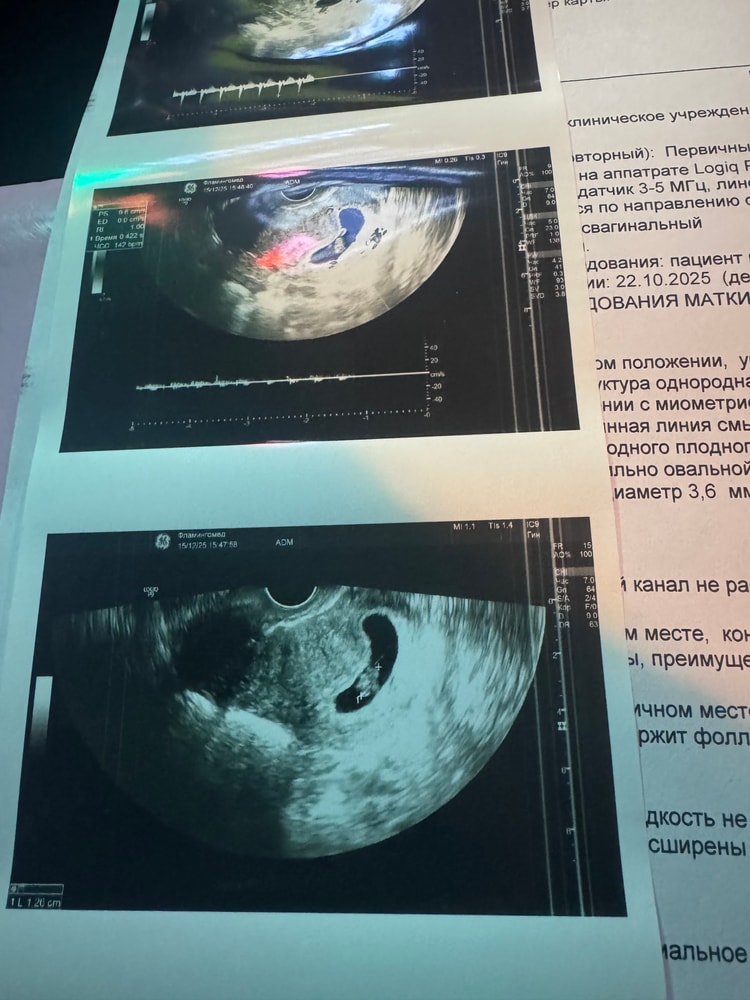

После 2 анэмбрионий, после бхб, еле переждав 6 и 7 недели, я услышала заветное "Эмбрион визуализируется, чсс 140"